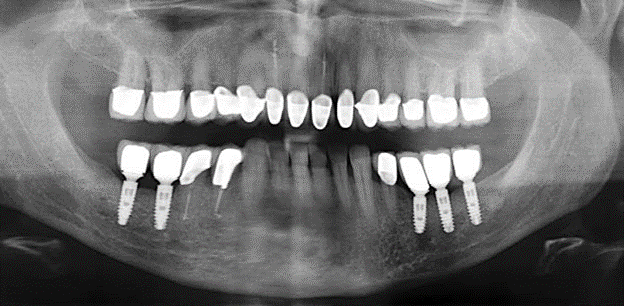

The ten-year check-up revealed no indications of advancing clinical attachment loss or peri-implant bone substance loss (Fig. 3).

Fig. 3: Panoramic radiograph after ten years with implants.